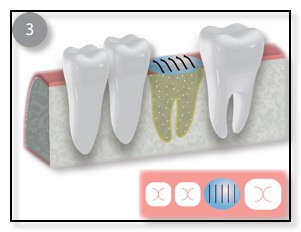

The other common type of bone graft for dental implants is a Ridge Augmentation, Ridge Enhancement, or Split Ridge. (See the diagram above.) Sometimes, when a patient has lost their tooth many months or years ago, the bone in that area has resorbed (the bone is lost). The remaining bone is too thin to support the dental implant. In such cases, Dr. Tsai would numb the area where the thin wall is, gently pull the gum tissue back, pack or place the bone graft in place, and suture the gum back into place. Sometimes Dr. Tsai will “split” the ridge and pack in the bone graft in order to thicken up the bone for the implant. This procedure typically takes 4-7 months to heal. Once the bone grafting has integrated or is healed, the dental implant can be placed.